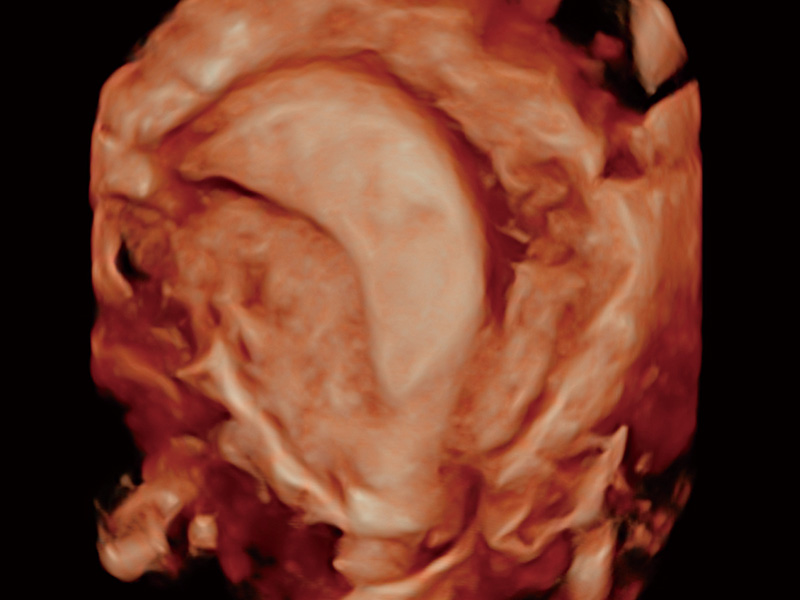

“生育问题”即关系民族复兴,也关系亿万家庭的幸福。随着婚育年龄推迟、社会压力增加等因素,越来越多人群也面临着“生不出、生不好”的问题。辅助生殖作为治疗不孕不育最有效的方法之一,也逐渐成为育儿新希望。而超声检查能为生殖需求人群的初诊评估提供宝贵的信息。 P20 Elite是开立医疗匠心打造的一款生殖应用型彩超。她继承开立医疗高端极光平台,突破性地将多款新型芯片及硬件模块进行整合,均衡了高端系统性能与小巧灵动机身。P20 Elite卓越的图像质量搭载专科探头,旨在为您提供全面的辅助生殖解决方案。

P20 Elite配备了丰富的生殖探头群和临床应用功能,在卵泡监测、穿刺取卵、胚胎移植、妊娠确认等领域,为生殖需求人群提供了新的临床机会,重新定义高端超声如何应用于生殖健康检查。